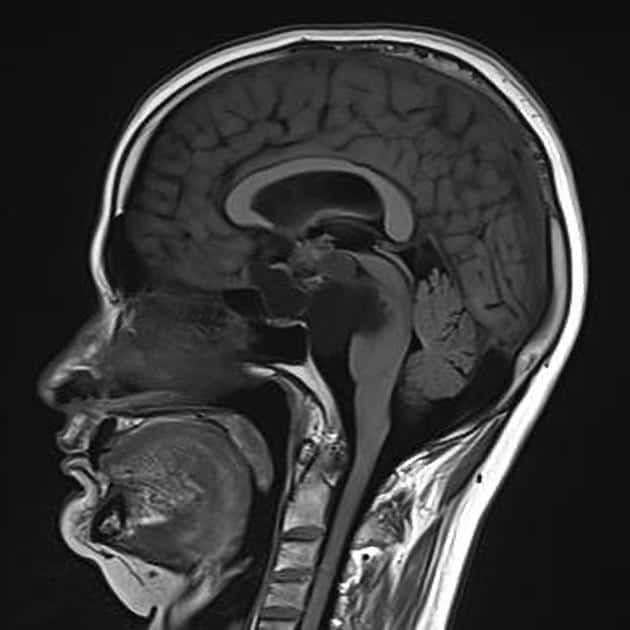

U sọ hầu

» Thông tin: Nam giới – 30 tuổi.

» Lâm sàng: Đau đầu.